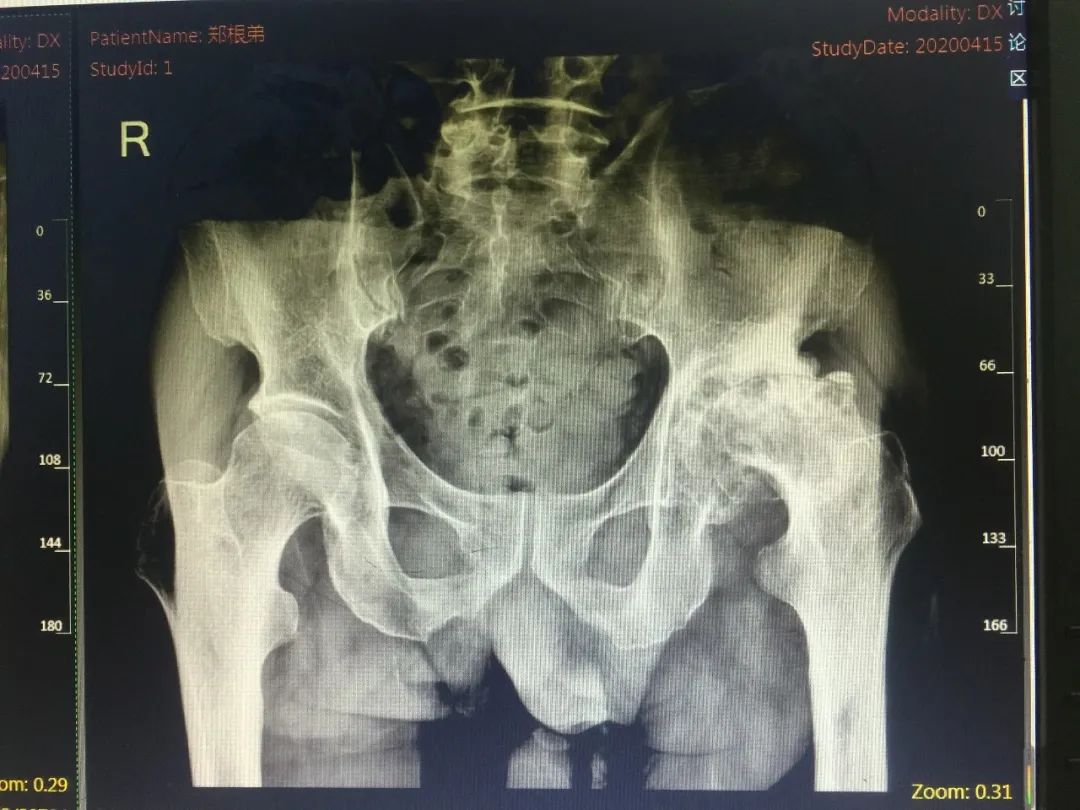

事情的原委是这样的,郑老伯今年85岁,4年前开始逐渐感觉左下肢走路时隐隐作痛,并且逐渐加重。曾经到市里几家大医院求医,医生都说老伯是因为年纪大了导致膝关节的磨损,让他吃点药,注意关节保养。但是治疗效果一直不好。随着时间的拖延,老伯的疼痛越来越严重,直到需要柱拐棍才能行走。平时身体硬朗的他心有不甘,不断地找医院求治,然而得到的答复都是膝关节老化,吃点药、打打针,但是还达不到手术的严重程度。抱着既然大医院不行,小医院也去试试看的心理,郑老伯于今年4月中旬由女儿陪着来到仁康医院,找到了徐煜院长。徐院长详细的询问了老伯的病史和整个疾病过程,仔细的给他做了检查。凭着丰富的临床经验和扎实的技术功底,徐院长敏锐地意识到郑老伯的毛病并不在膝关节,而是出在髋关节上。随后的影像检查,完全证实了徐院长的判断——左侧髋关节的严重骨关节炎,需要手术治疗。随后,郑老伯住进了病房,并由徐院长亲自操刀行全髋关节置换手术。尽管老伯的关节病变十分严重,大量的骨质增生和严重的关节变形,但是手术做得非常成功。术后在全体医护人员的精心治疗护理下,老伯术后5天就逐渐下地行走。

术前术后对比